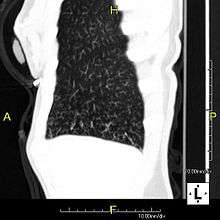

The main consequence of impaired ciliary function is reduced or absent mucus clearance from the lungs, and susceptibility to chronic recurrent respiratory infections, including sinusitis, bronchitis, pneumonia, and otitis media. Progressive damage to the respiratory system is common, including progressive bronchiectasis beginning in early childhood, and sinus disease (sometimes becoming severe in adults). However, diagnosis is often missed early in life despite the characteristic signs and symptoms.[1] In males, immotility of sperm can lead to infertility, although conception remains possible through the use of in vitro fertilization and, as well as this, there have been reported cases where sperm were able to move.[2] Trials have also shown that there is a marked reduction in fertility in female sufferers of Kartagener's Syndrome due to dysfunction of the oviductal cilia.[3]

Many affected individuals experience hearing loss and show symptoms of glue ear which demonstrate variable responsiveness to the insertion of myringotomy tubes or grommets. Some patients have a poor sense of smell, which is believed to accompany high mucus production in the sinuses (although others report normal - or even acute - sensitivity to smell and taste). Clinical progression of the disease is variable with lung transplantation required in severe cases. Susceptibility to infections can be drastically reduced by an early diagnosis. Treatment with various chest physiotherapy techniques has been observed to reduce the incidence of lung infection and to slow the progression of bronchiectasis dramatically. Aggressive treatment of sinus disease beginning at an early age is believed to slow long-term sinus damage (although this has not yet been adequately documented). Aggressive measures to enhance clearance of mucus, prevent respiratory infections, and treat bacterial superinfections have been observed to slow lung-disease progression. Although the true incidence of the disease is unknown, it is estimated to be 1 in 32,000,[4] although the actual incidence may be as high as 1 in 15,000.